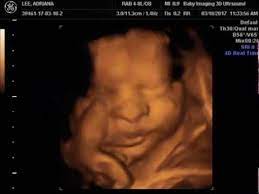

It is a fun time for the ultrasound as many times you will see movements like smiling, eyes blinking, hands moving, and many other movements. If you are having multiples this is also a good time to capture 3d pictures of the babies. At this stage, the baby has put on some weight and filled out to make features more visible, yet still enough fluid in front of baby's face to obtain great images. Your baby has to hold very still so that the high frequency sound waves have time to form around your baby's features. Snuggling cord at 18 weeks. The 4d ultrasound uses sound waves to create this moving image. Up to 32 weeks there generally still room for the baby to move. Baby impressions is an elective 3d 4d ultrasound imaging facility. At 18 weeks, your baby has mastered the art of yawning, along with hiccuping, which you may feel soon. You learn today about your baby development, prenatal care (doctor visits) and fetal ultrasound at 31 weeks. I'm only at 31 weeks, but i had that 4d/3d u/s and yes, baby looked totally deformed. Sounds like you have a very active baby! We require that all mothers have documentation of their prenatal care and most recent diagnostic ultrasound.

At this stage, the baby has put on some weight and filled out to make features more visible, yet still enough fluid in front of baby's face to obtain great images. I'm only at 31 weeks, but i had that 4d/3d u/s and yes, baby looked totally deformed. We just went yesterday at 31 weeks 4 days. In fact, it's quite similar to 4d ultrasound. Up to 32 weeks there generally still room for the baby to move. View images & learn more 30 week ultrasound The 4d ultrasound uses sound waves to create this moving image. Sofort kostenlos und ohne anmeldung anfragen

We can also broadcast the session 5d hd live to anywhere in the world to share this precious time. You will get 2d, 3d and 4d images all recorded on your very own digital storage. Plus, learn about the major reproductive developments at this stage. Cutest chubby cheeks on our little one. It creates an effect that is similar to watching a live. 3d & 5d ultrasound images and 4d ultrasound video can be obtained at any stage. Yawns, stretches, and even smiles are often captured in our 3d & 4d ultrasounds, and we look forward to sharing this miracle with you as well! About press copyright contact us creators advertise developers terms privacy policy & safety how youtube works test new features press copyright contact us creators.